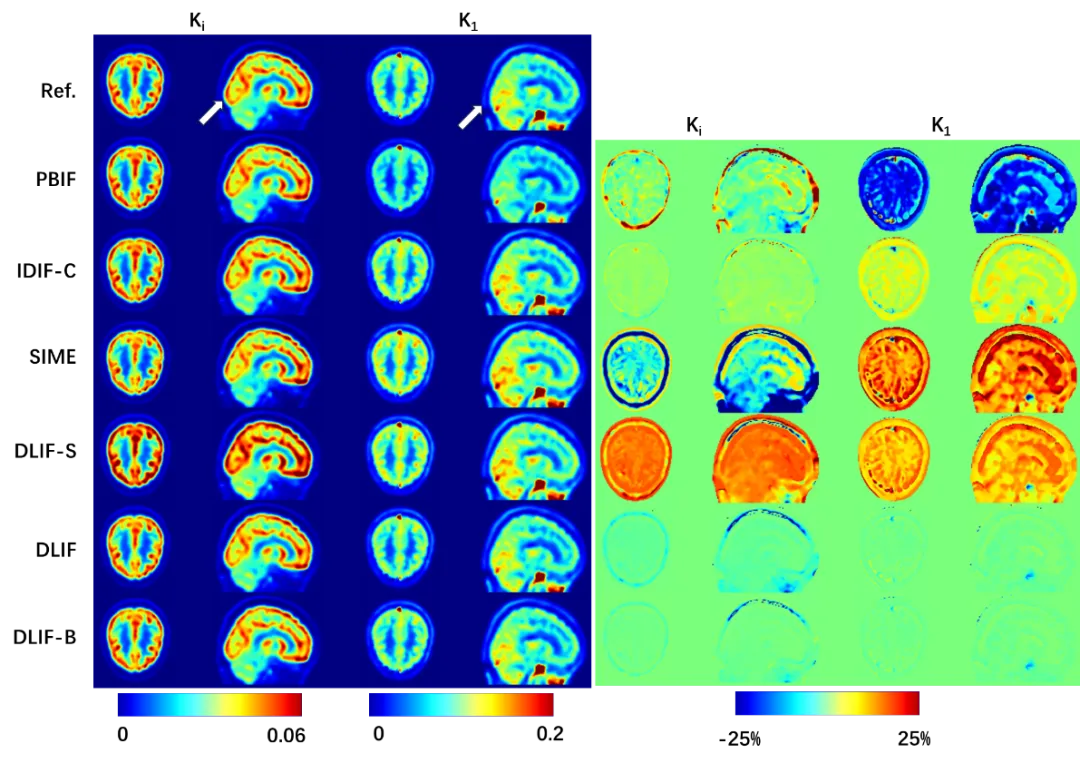

從視覺和定量兩個方面來看,參數(shù)圖像也與參考圖像高度吻合(圖3)。這些結(jié)果證實了無創(chuàng)且準確地估計血流輸入函數(shù)的可行性,該方法適用于常規(guī)的短視野或?qū)S媚X部掃描PET系統(tǒng),并且無需進行部分容積校正。通過精準計算獲得的全局灌注、凈流入、凈代謝和其他微觀參數(shù),有助于推動在廣泛的神經(jīng)和精神疾病中大腦代謝功能的研究,進而輔助制定更有效的治療策略。

圖3 展示了使用不同方法估計的輸入函數(shù)所計算的K1/Ki圖像(左)??梢杂^察到,使用所提出的方法(DLIF)估計的參數(shù)圖像與參考圖像最為接近,且誤差值范圍最?。ㄓ遥?。